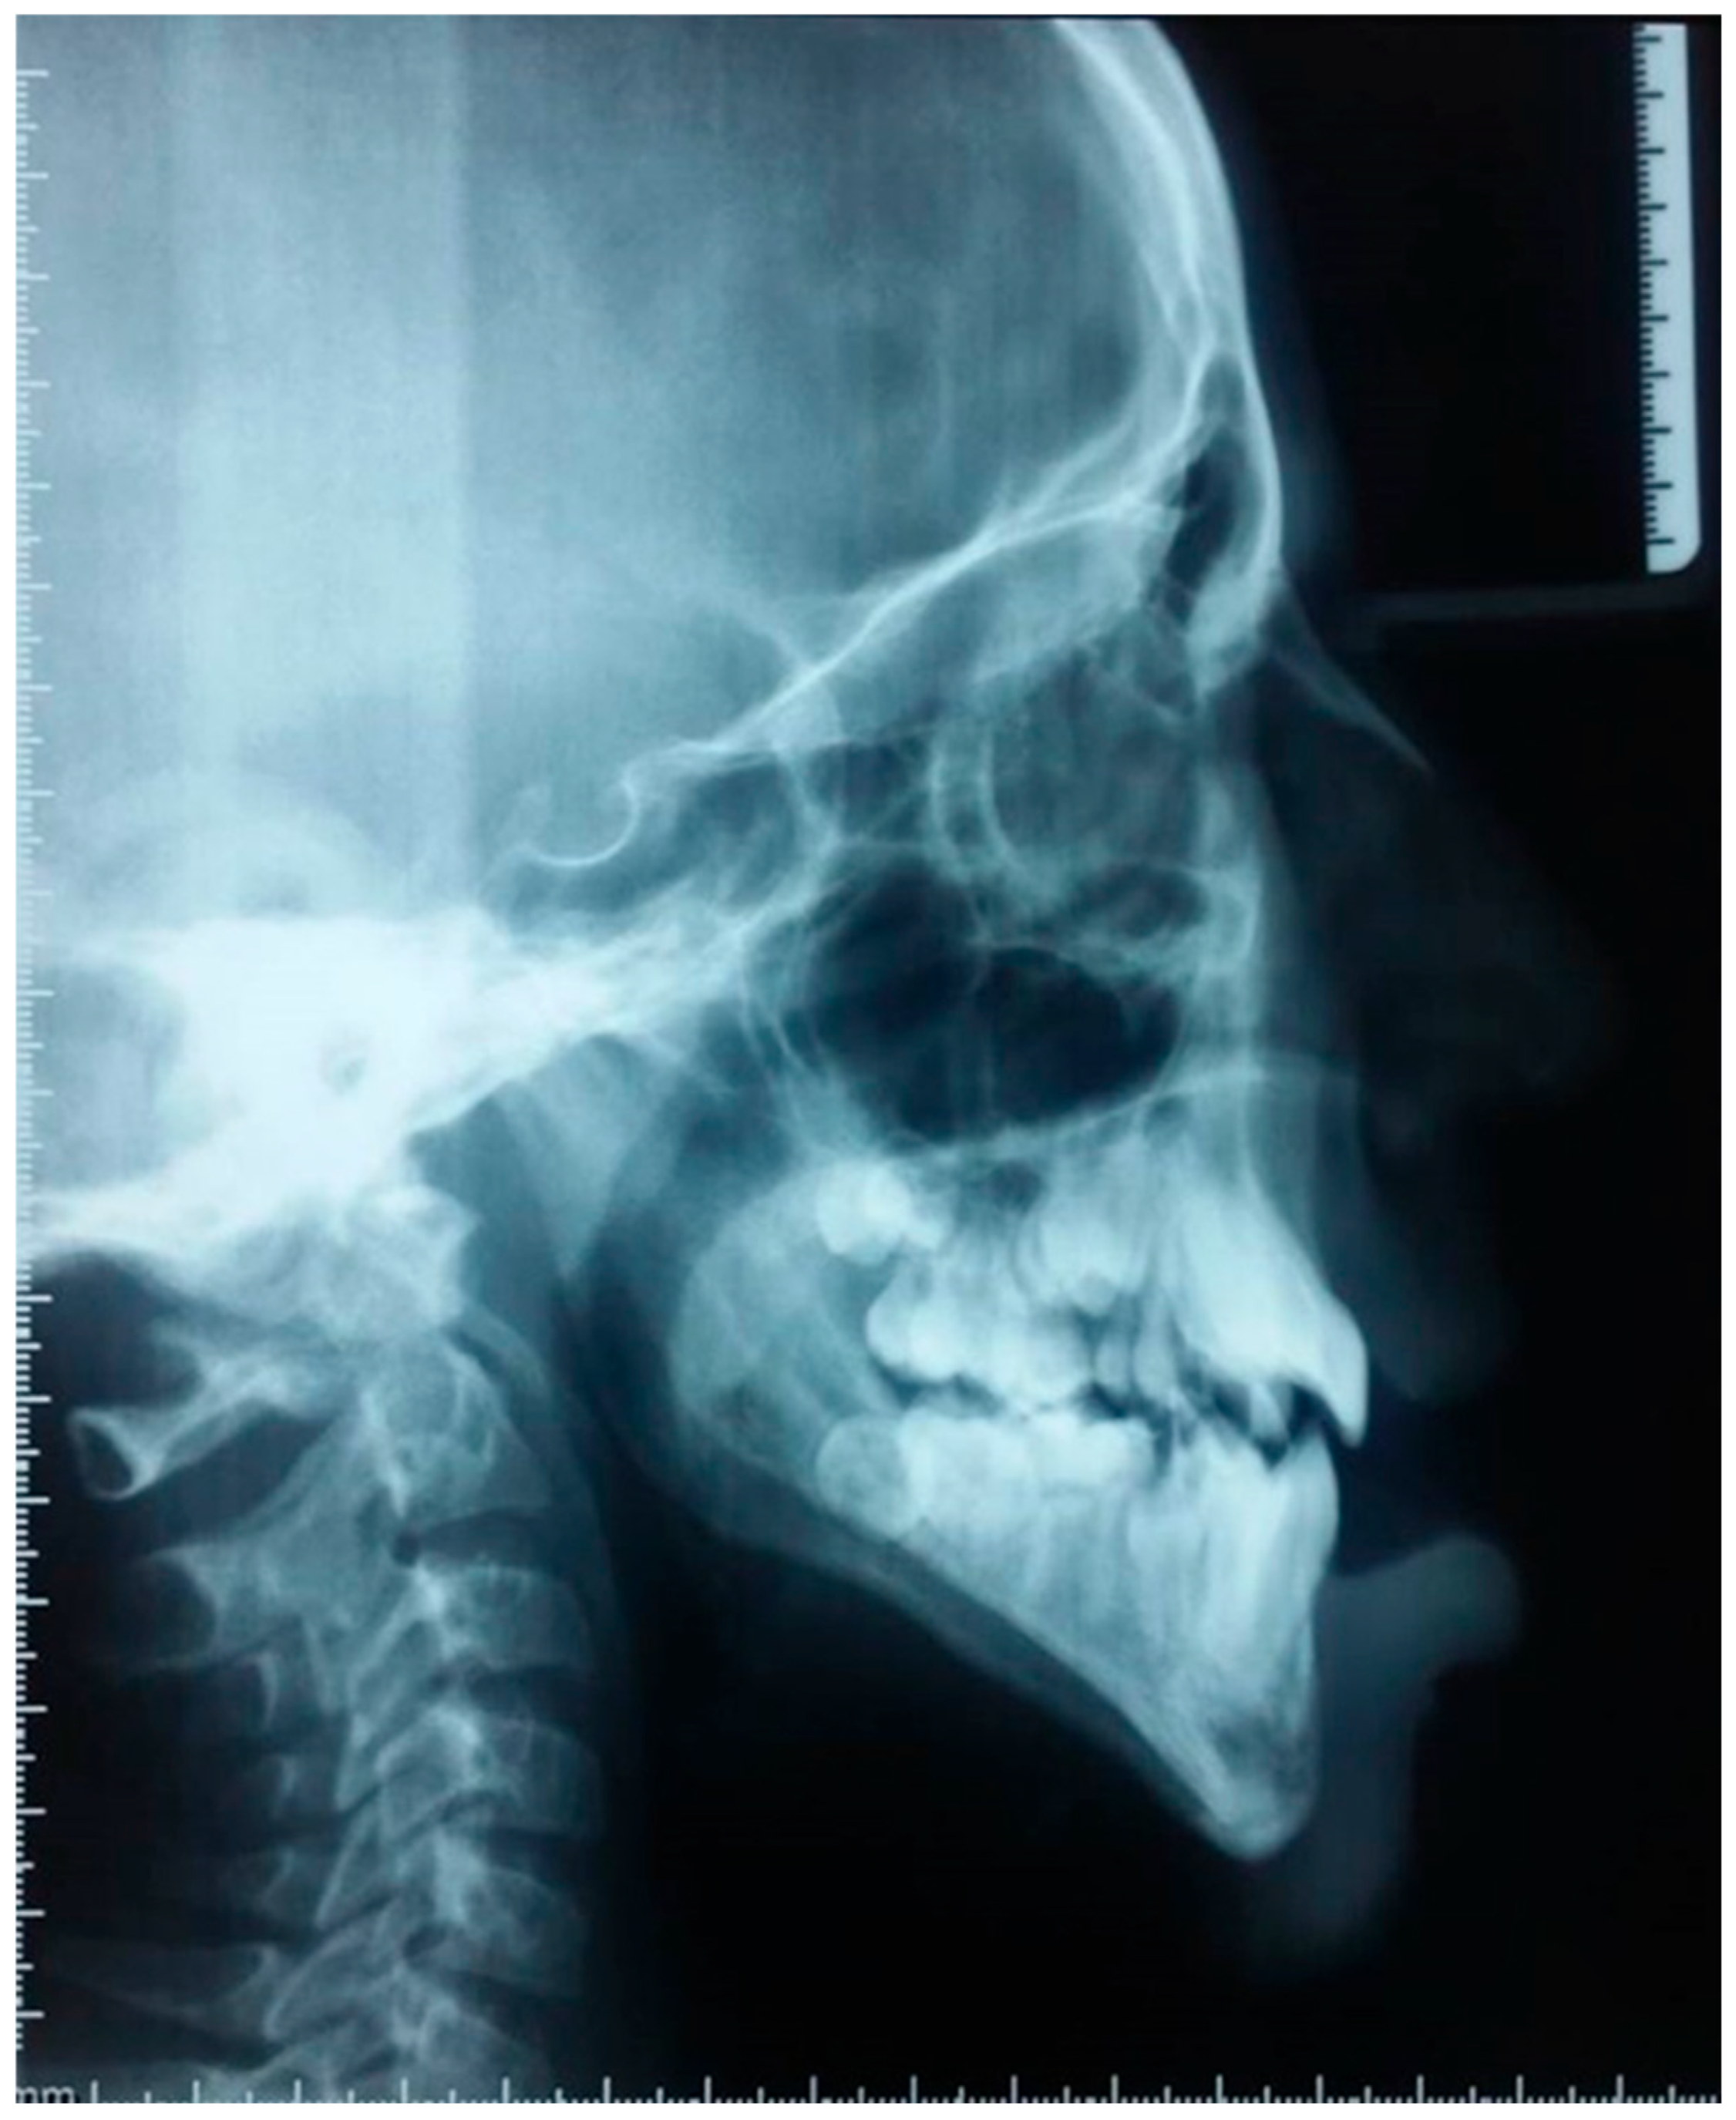

2.5. Radiographic Examination

- Sagittal Skeletal Relationship: The SNA angle (70°) indicates significant maxillary retro position. The SNB angle (71°) confirms true mandibular retrognathia. Despite this retrognathic mandible, the ANB angle is on the lower end of normal (1°), and the AoBo measurement is severely negative (−7 mm). This combination unequivocally establishes a skeletal Class III relationship.

- Vertical Skeletal Relationship: The most striking finding is a severely hyperdivergent growth pattern, evidenced by the drastically increased GoGn-SN angle (53° compared to a norm of 32° ± 5).

- Dental Compensations: The incisor analysis revealed compensatory adaptations. The upper incisors are proclined (I/NA: 24°) and protruded (itoNA: 7 mm), while the lower incisors are retroclined (I/NB: 19°) and retruded (itoNB: 1 mm), classic mechanisms in skeletal Class III cases.